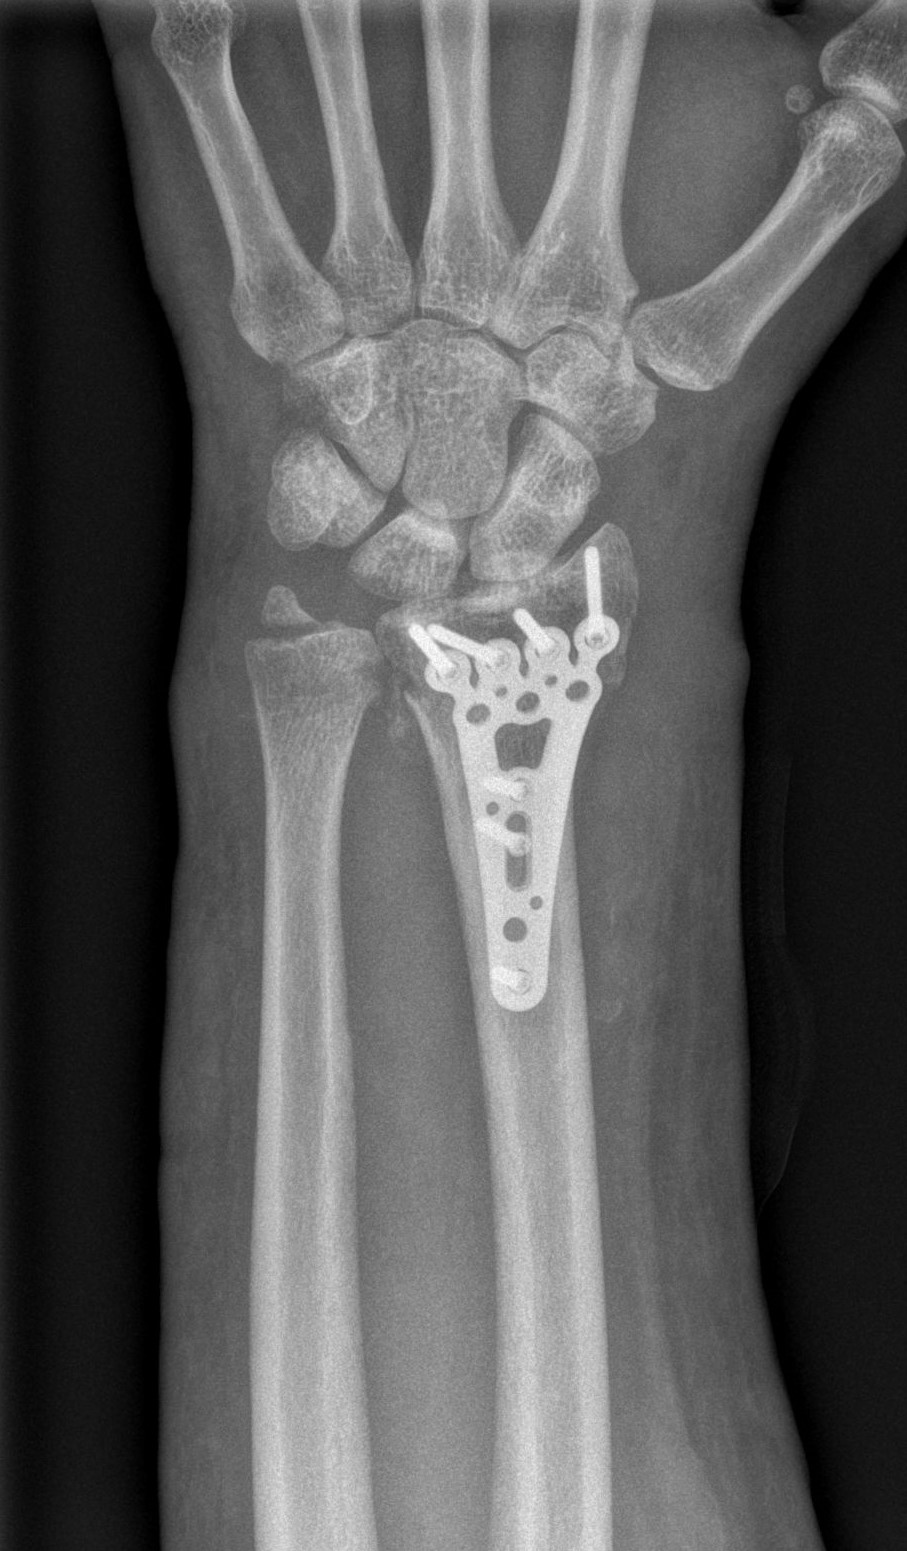

Successful surgery to reduce and fixate with the plate of neglected, displaced fracture of the distal radius

Treatment of neglected, displaced or united distal radial fractures (DRFs) is difficult, because it requires either wedging the almost consolidated fracture and reduction to the correct position, or cutting the united bone and putting it in the correct position (corrective osteotomy). Both treatments are associated with the risk of failure and complications. The paper presents a case of almost fully united DRF in a man, in whom 5 weeks after the injury, and after unsuccessful primary fixation with K-wires, the bone fragments were surgically wedged, aligned and fixed with a palmar plate. The result of treatment after 2 months was satisfactory. Early surgery allowed for a significant shortening of the recovery period and allowed the patient to return to work.